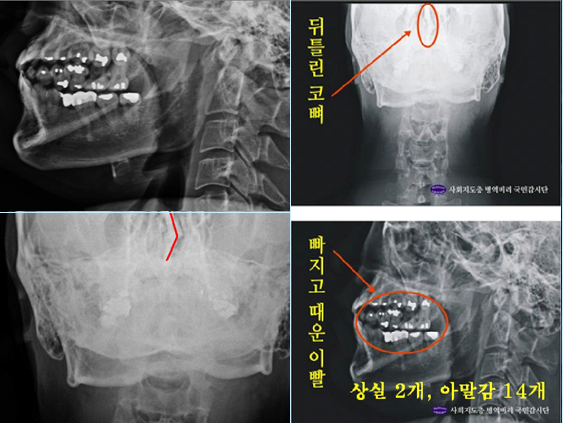

이들 엑스레이를 판독한 국내 의료진들은 “2011년 12월 자생병원에서 찍은 엑스레이에서는 우측 제1늑골에 석회화 소견이 발견되고, 흉추 1번 극상돌기 역시 수직방향으로 배열돼 있지만, 공군 엑스레이와 비자발급용 엑스레이에서는 석회화 현상이 발견되지 않았고, 극상돌기 역시 오른쪽 방향으로 배열돼 있다”고 지적하고 있다.

나아가 의사들은 박주신씨 명의의 엑스레이에 대한 비교·판독 결과, ▲흉추 1번, 경추 7번의 추궁판과 극돌기 밑단의 형태 ▲견갑골 견봉의 두께 ▲견갑골 오구돌기와 관절와(關節窩) 평면과의 각도 등에서 차이점이 발견된다고 지적하고 있다.

2011년 박주신씨에 대한 병역비리 의혹이 처음 불거진 뒤 지금까지 박주신씨의 신체를 촬영한 것으로 알려진 엑스레이는 모두 3개가 있다.이 가운데 언론을 통해 널리 알려진 자생병원 엑스레이(촬영일자 2011년 12월 9일)는, 박주신씨 본인이 아닌 제3자의 신체를 촬영한, 이른바 ‘대리신검자 엑스레이’라는 의심을 받고 있다.

- ▲ 박주신씨 명의의 자생병원 엑스레이. ⓒ 뉴데일리DB

반면 지난해 12월부터 시작된 양승오 박사 등 시민 7명에 대한 공직선거법 위한 공판을 통해 새롭게 밝혀진, 박주신씨의 ‘공군훈련소 입소 당시 엑스레이’(촬영일자 2011년 8월 30일, 이하 공군 엑스레이)와, 주신씨가 ‘비자발급을 위해 촬영한 세브란스병원 엑스레이’(촬영일자 2014년 7월 31일, 이하 비자발급용 엑스레이)는 각각 박주신씨 본인의 신체를 촬영한 것으로 받아들여지고 있다.

- ▲ 박주신씨 공군훈련소 입소 당시 촬영된 엑스레이. ⓒ 뉴데일리DB

- ▲ 박주신씨가 지난해 7월 비자발급을 위해 촬영한 엑스레이. ⓒ 뉴데일리DB

이들 세 개의 엑스레이는 모두 박주신씨의 신체를 촬영한 것으로 알려져 있기 때문에, 이들 엑스레이에 대한 판독결과 피사체를 동일인으로 볼 수 없는 유의미한 차이점이 발견된다면, 이는 박주신씨의 대리신검 혹은 영상자료 바꿔치기 의혹을 뒷받침하는 결정적 단서가 된다.

세계적 권위를 인정받은 영상의학 전문의인 양승오 박사(동남권원자력의학원 암센터 핵의학과 주임과장)와 치과의사 김우현씨 등 박주신씨 병역비리 의혹을 주장해 온 시민들은, 위에서 언급한 세 개의 엑스레이에 대한 비교 판독 결과, 이들 엑스레이를 같은 사람의 것으로 볼 수 없는 차이점을 발견하고 이를 재판부에 증거자료로 제출했다.

‘석회화’와 ‘극상돌기’

‘석회화’란 나이가 들어 뼈에 발생하는 퇴행성 증상의 하나로 질병이라고 볼 수는 없지만 한 번 생기면 없어지지 않으며, X-Ray를 통해 확인할 수 있는 것으로 알려졌다.

-

- ▲ ▲박주신의 자생병원 X-Ray(왼쪽)과 공군 X-Ray(오른쪽). 자생병원의 엑스레이에서는 오른쪽 제1늑골부위에 '석회화'현상이 보이지만 공군엑스레이에선 보이지 않는다. ⓒ 뉴데일리DB

박주신씨의 자생병원 X-Ray를 보면, 오른쪽 제1 늑골부위에 ‘석회화’ 현상이 나타난다. 그러나 주신씨가 공군 입대 당시 찍은 X-Ray에는 이런 모습이 전혀 보이지 않는다.

이런 차이에 대해 양승오 박사의 변호인인 차기환 변호사 등은 "각각의 X-Ray를 찍은 사람이 동일인이 아니라는 것을 입증한다"고 설명했다.

‘극상돌기’의 경우에도 차이점은 명확히 드러난다.

변 호인 측은 “공군에서 찍은 엑스레이와 비자발급을 위해 찍은 엑스레이에서는 피사체의 제 1흉추 극상돌기가 오른쪽으로 휘어있지만, 자생병원에서 찍은 영상에서는 정방향으로 나온다”며, “박주신씨가 공군에 입대해 찍은 엑스레이와 세브란스 공개신검에서 나타난 피사체의 의학적 차이가 명확해 동일인이라고 인정할 수 없다”고 지적했다.

우리가 흔히 등을 만지면, 가운데 뾰족하게 솟아난 부분이 바로 ‘극상돌기’다.

흉추를 비롯해 모든 척추에 존재하며, 흉추에 외상이나 수술, 질병 등이 없었던 근접한 기간 동안 촬영된 엑스레이에서 극상돌기의 형태가 명확하게 다를 경우, 다른 개체라고 판단할 의학적 근거가 된다.

▲ 자생병원 엑스레이와 박주신씨가 공군훈련소 입소 당시 찍은 엑스레이에서 나타나는 분명한 차이점(‘석회화 현상’과 ‘극상돌기’),